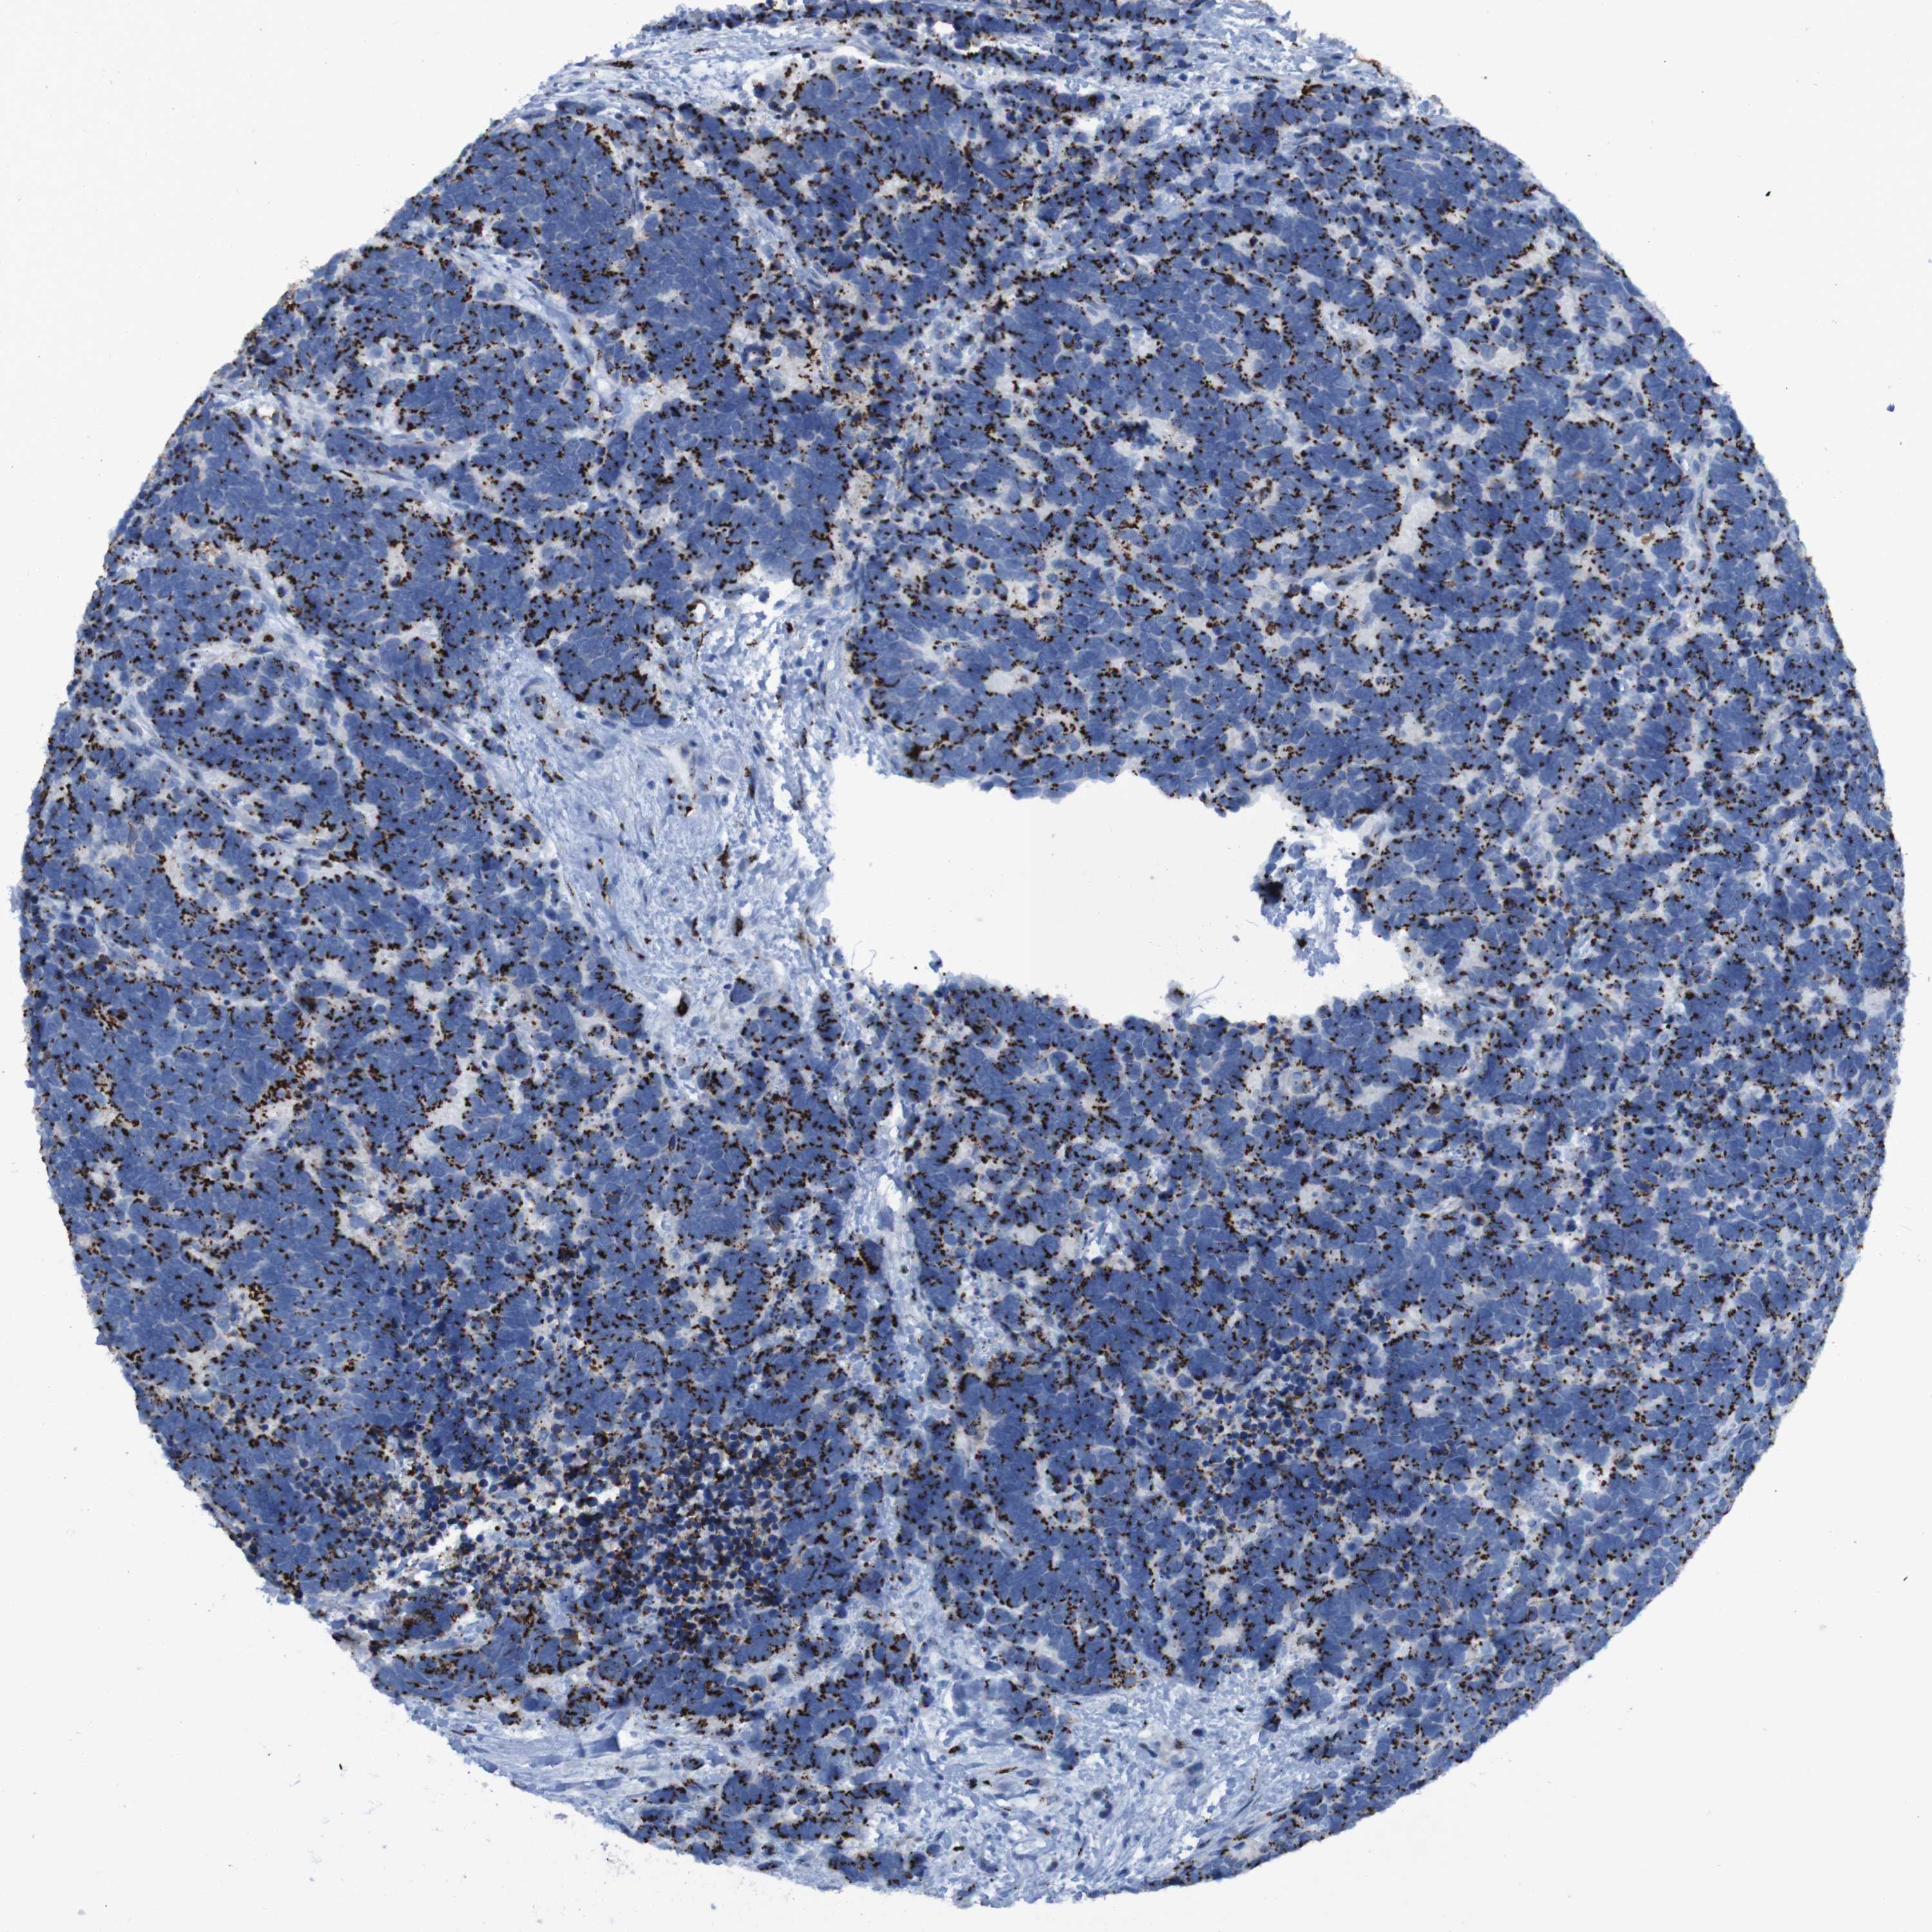

CARCINOID - Protein expressioni

A mouse-over function shows sample information and annotation data. Click on an image to view it in a full screen mode. Samples can be filtered based on level of antibody staining by selecting one or several of the following categories: high, medium, low and not detected. The assay and annotation is described here.

Antibody stainingi

Antibody staining in the annotated cell types in the current human tissue is reported as not detected, low, medium, or high, based on conventional immunohistochemistry profiling in selected tissues. This score is based on the combination of the staining intensity and fraction of stained cells.

Each image is clickable and will lead to virtual microscopy that enables deeper exploration of all samples and also displays staining intensity scores, fraction scores and subcellular localization as well as patient and tissue information for each sample.

Antibody HPA011929

Staining

Medium

Moderate

75%-25%

Cytoplasmic/membranous

Carcinoma, NOS